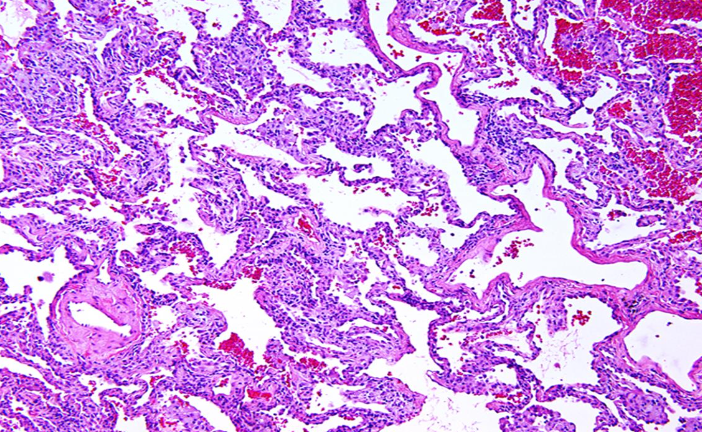

Asma

Solo ver